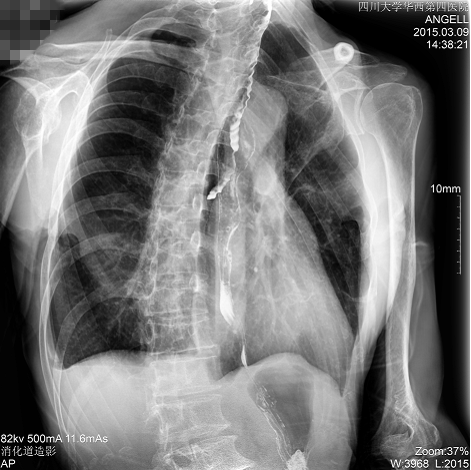

如下圖所示:該患者因吞咽時感到很難受,進食時也經(jīng)??人怨示歪t(yī)診斷。華西醫(yī)院醫(yī)生使用動態(tài)DR為病人進行消化道造影診斷,要求他吞鋇后發(fā)現(xiàn),食道各段通過順利,形態(tài)規(guī)則,雙側(cè)梨狀窩不對稱左側(cè)稍淺,多次吞咽動作后,仍見鋇劑滯留,并見鋇劑進入氣管,屬于會厭征陽性。會厭功能紊亂,鋇劑進入了氣管。

圖為斜位:通過動態(tài)影像可以清楚看到鋇劑進入了支氣管道